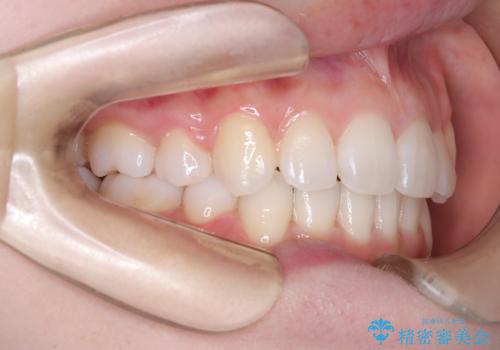

【審美ワイヤー】八重歯を治したい。

- 左上の犬歯の凸凹や正中のずれを主訴に来院されました。

凸凹を治すために、上下左右の小臼歯を抜歯してワイヤー矯正を行いました。

患者様には、顎間ゴムを使用していただくことで、2年という期間で治療を終了することができました。